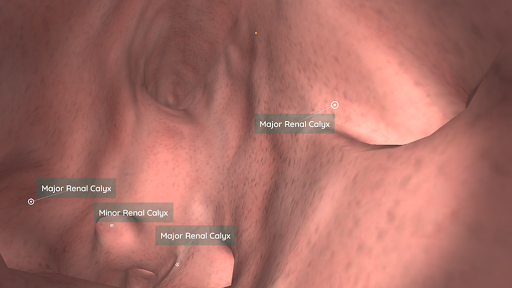

En utilisant la réalité virtuelle, vous serez capable de naviguer le long des structures anatomiques, devenant une partie de l'anatomie humaine: circulatoire, respiratoire, digestive, urinaire, lacrymale et système reproducteur féminin.

En mode Réalité virtuelle, un appareil mobile (smartphone) doit être inséré dans un gadget de réalité virtuelle pour profiter d'une expérience totalement immersive. L'utilisateur peut interagir avec les commandes de navigation et les éléments d'information anatomiques en les visant.

Ceci est une version récemment rénovée d'Anatomyou VR. Les fonctionnalités incluent: - Anatomie humaine plus réaliste, améliorant les modèles et les textures. - Meilleure interaction de l'utilisateur en mode VR et en mode plein écran. - Des menus et des images entièrement rénovés permettent une navigation intuitive. - Contenu clinique supplémentaire validé par nos experts. - Les utilisateurs précédents doivent accepter certaines autorisations (GoogleVR SDK). Nous avons mis beaucoup d'efforts dans cette mise à jour, j'espère que vous l'apprécierez!